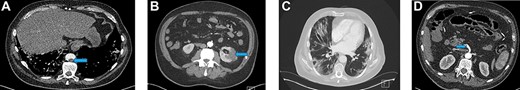

Blood investigations showed an elevated WCC, a low lymphocyte count and elevated CRP. His prothrombin and thrombin times were also prolonged (Table 1). A CT scan demonstrated filling defects in the descending thoracic and abdominal aorta (Fig. 2A) and superior mesenteric artery (SMA) suggestive of acute thromboembolic phenomena. There was no sign of ischaemic bowel. A wedge-shaped peripheral hypodensity was seen at the mid-pole of the left kidney (likely to be a renal Infarct) (Fig. 2B). A CT of the chest showed patchy and ground-glass shadowing (Fig. 2C).

(A) Filling defect in aorta (blue arrow). (B) Left renal infarct (blue arrow). (C) CT-thorax showing pulmonary changes. (D) Thrombus in the distal SMA (blue arrow)

A repeat CT showed a SMA thrombus (Fig. 2D). Urgent angiogram and catheter-directed thrombolysis of the SMA was unsuccessful and the decision was made to operate. Exploratory laparotomy revealed a gangrenous segment of ileum necessitating resection of ~30 cm of small bowel. Re-look laparotomy at 48 hours showed no progression of ischaemia and thus anastomosis of the bowel ends was performed.